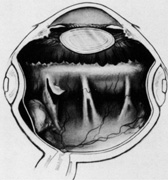

Current cryotherapy instrumentation employs expansion of high-pressure nitrous oxide at the tip of a probe generating temperatures as low as 89°C. The temperature effect is confined to the tip of the probe by an insulating sleeve. A probe 2.0 to 2.5 mm in diameter usually is used for retinal work. Treatment of retinal breaks and pathologic conditions requires accurate placement of the cryoprobe tip. The surgeon must be certain that the indentation visualized with the indirect ophthalmoscope is the tip of the probe and not the shaft. Confusion between the tip and the shaft of the cryo-probe can cause inadvertent posterior freezes.33 To minimize the possibility of this complication, the surgeon must indent only with the tip of the cryoprobe (Fig. 10). It is also helpful to perform the first freezes at the most anterior aspect of the area requiring treatment to assess both location and intensity of treatment.

Fig. 10. A. Inadvertent posterior placement of cryoprobe tip caused by visualization of cryoprobe shaft. B. Correct placement of cryoprobe tip.